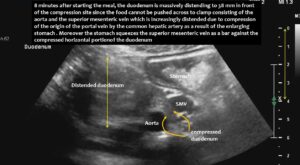

The superior mesenteric vein appeared normal when the stomach was empty, but showed enormous 5-fold enlargement of its transsectional area after food was consumed. The enlarged vein prevented food from passing across the aorta, as the stomach pushed the superior mesenteric vein against the duodenum, narrowing the passage to such an extent that the descending duodenum enlarged to 38 mm (the usual width is less than 20 mm). The patient reported substantial pain in the area of the distended duodenum, below the right rib cage.

- Due to the limited space restricted by the flat lower thoracic aperture, the volume of food and gas in the stomach after a meal was sufficient to push the liver and its main artery, which runs along the lower surface of the liver, against the root of the portal vein. This produced significant enlargement of the portal vein’s feeding vessels, primarily the superior mesenteric vein.

- Compared to the fasting state, this vein enlarged fivefold and formed an abutment for the aorta, both of which squeezed the horizontal portion of the duodenum and obstructed the passage of food. This caused postprandial nausea and vomiting, as well as an inability to be fed via a nasogastric tube.

Here, the unique mechanism causing compression of the duodenum by the enlarged superior mesenteric vein is demonstrated. In contrast to conventional SMA syndrome, the superior mesenteric vein acts as a pillar against which the aorta presses, thus obstructing the duodenum. It is important to be aware of the variability in the position of the superior mesenteric artery in patients with a flat abdominal cavity. When the stomach is full, it may shift further to the left (or right) of the SMA than in the fasting position.

Enlargement of the superior mesenteric vein can be observed as early as five minutes after eating, progressing to fivefold enlargement of the transsectional area after seven minutes.